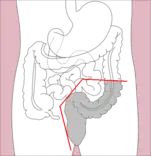

- Right hemicolectomy and left hemicolectomy refer to the resection of the ascending colon (right) and the descending colon (left), respectively. When part of the transverse colon is also resected, it may be referred to as an extended hemicolectomy.[5]

Right hemicolectomy

Right hemicolectomy Right extended hemicolectomy

Right extended hemicolectomy Left hemicolectomy

Left hemicolectomy Extended left hemicolectomy

Extended left hemicolectomy - Transverse colectomy is also possible, though uncommon.